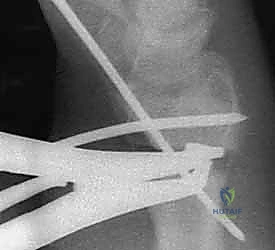

2. الشق الجراحي والوصول للعظم (Surgical Approach)

يقوم الدكتور هطيف بعمل شق جراحي دقيق (غالباً من الجهة الأمامية للرسغ - Volar Approach). يتم إبعاد الأوتار والأعصاب (مثل العصب الأوسط) والأوعية الدموية بمنتهى الحذر باستخدام تقنيات الجراحة المجهرية لحمايتها من أي ضرر.

3. قص العظم التصحيحي (The Osteotomy)

بناءً على التخطيط الثلاثي الأبعاد المسبق، يستخدم الدكتور هطيف مناشير عظمية دقيقة جداً لعمل شق في العظم في نقطة التشوه الأصلية. يتم فتح العظم وتعديل زاويته واستعادة طوله الطبيعي.